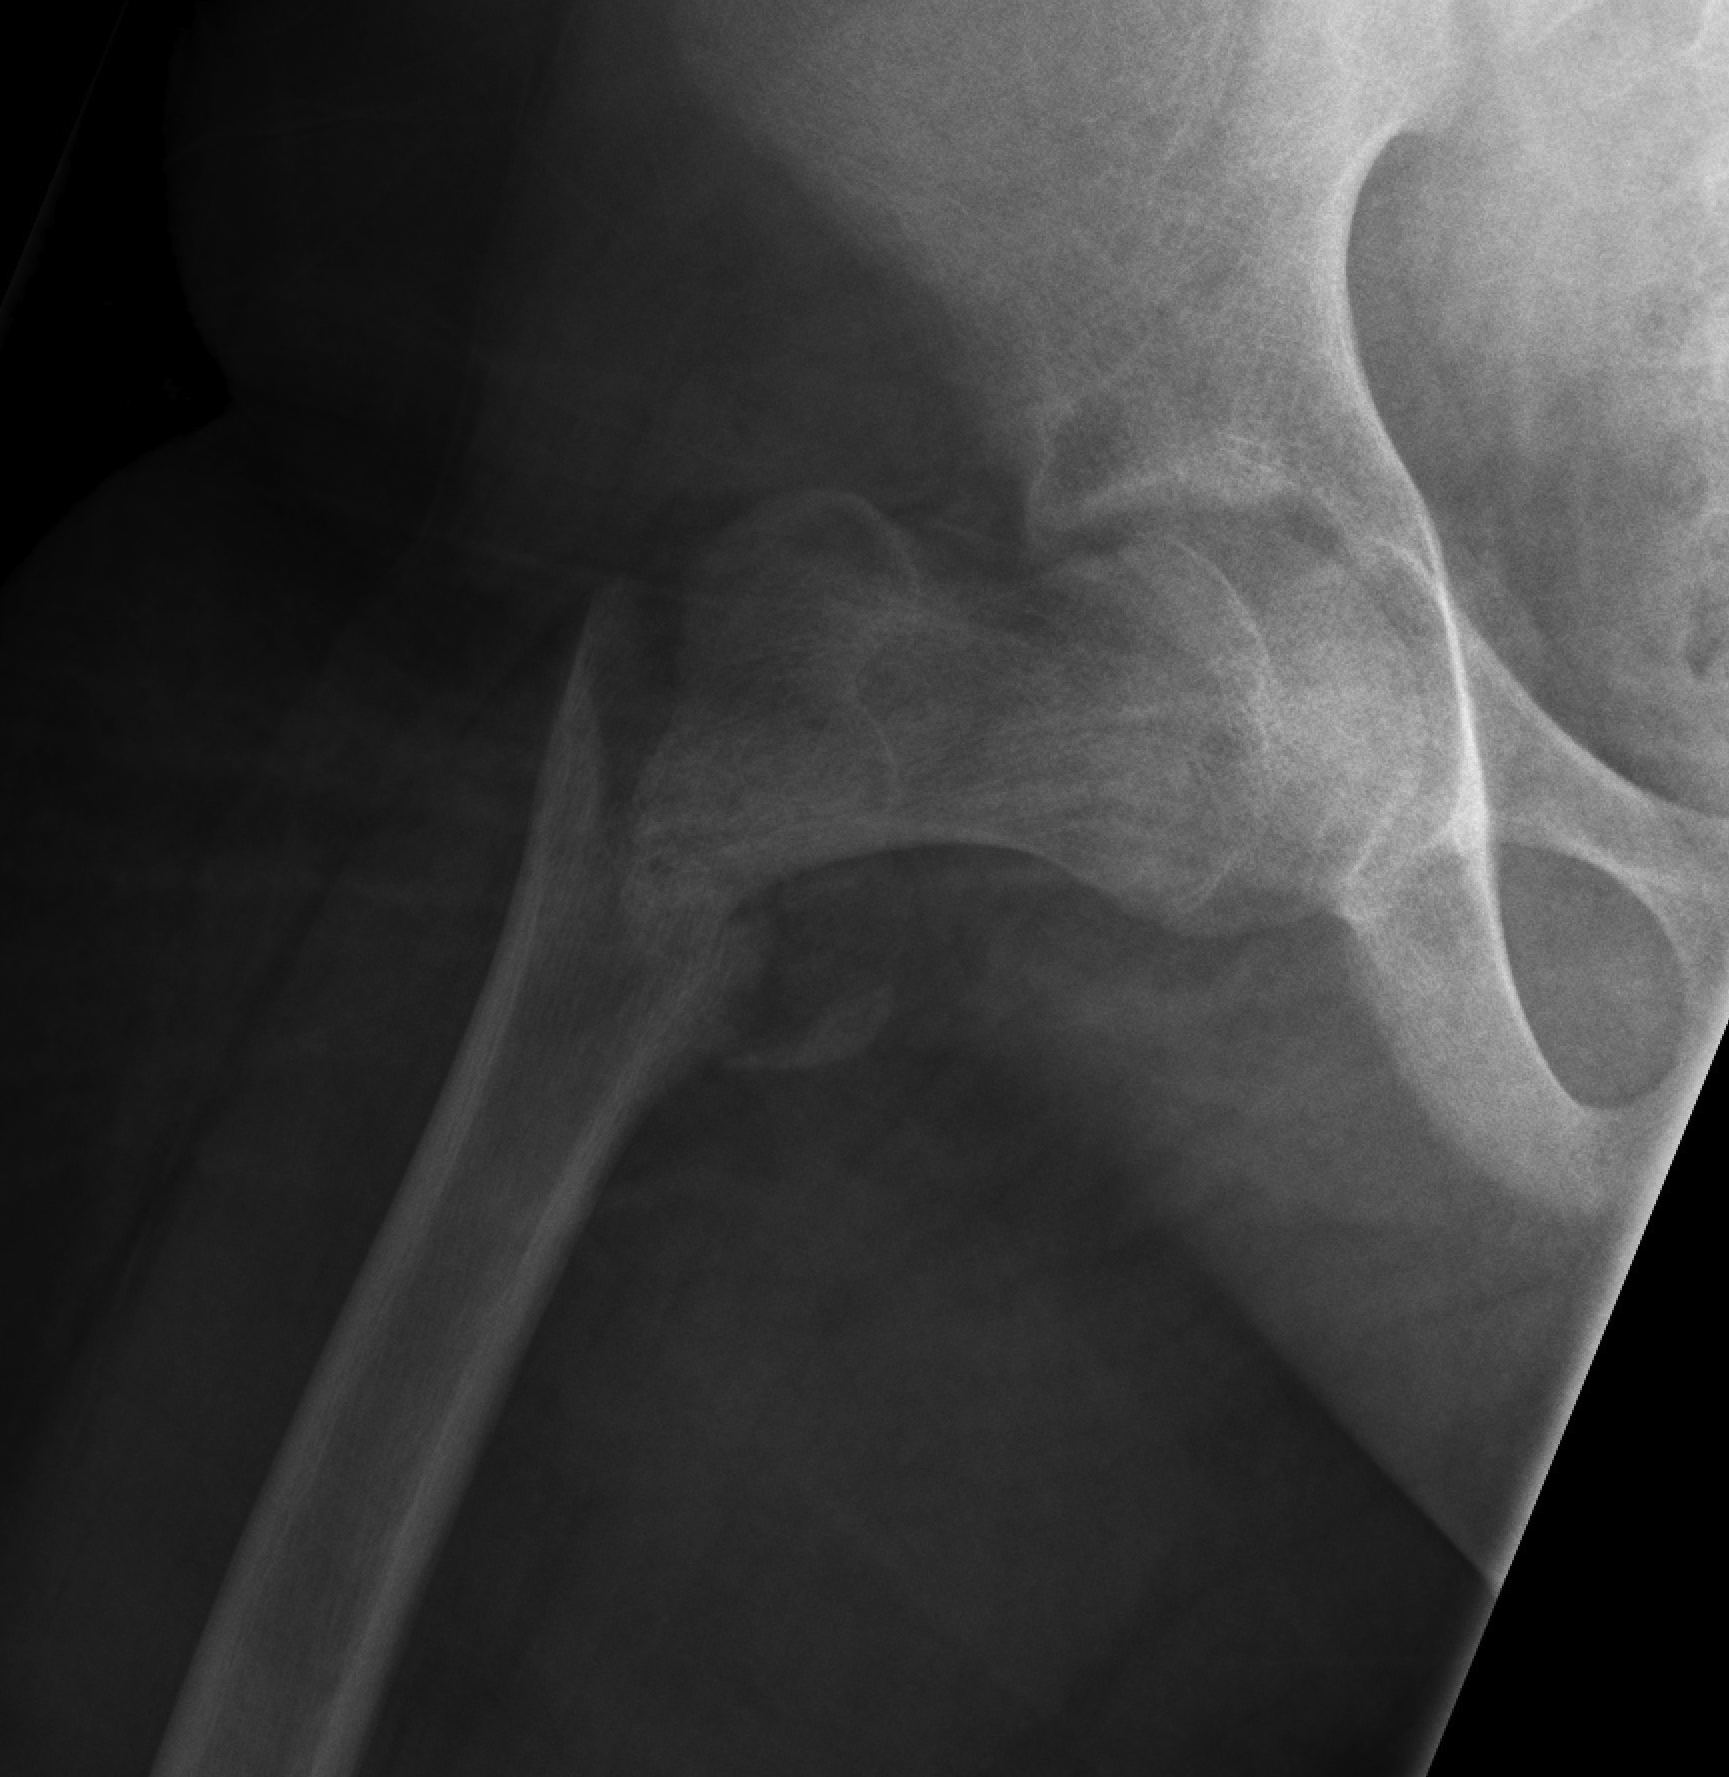

Delbert Classification

Type 1

- transepiphyseal separation / fracture

- rarest

- associated with hip dislocation

- AVN 100%

Type 2

- transcervical fracture

- commonest 50%

- AVN 50%

Type 3

- basicervical

- second most common 30%

- AVN 30%

Type 4

- intertrochanteric fracture

- AVN 10%